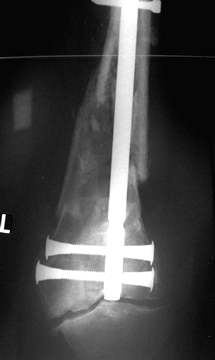

auch in der Seitaufnahme achsengerechte Stellung der Fraktur